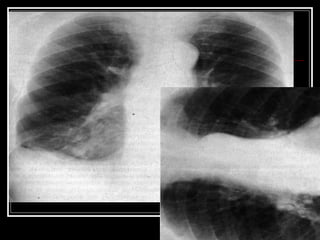

DERRAME PLEURAL DERECHO

DERRAME TABICADO

PAQUIPLEURITIS